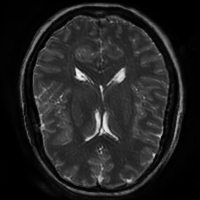

4.4 Qualitative Evaluation

In Figure 5 we analyze the prediction quality of our and compared approaches in a qualitative way. Considering modality propagation in MRI, we see that usage of uncertainty-aware patch invariance (UAPI) gives a better detailed weighting of the cerebrospinal fluid in the middle of the brain. In general, employing patch invariance yields better preservation of fine structures. This observation also applies to accelerated MRI enhancement. In particular, CUT and UAPI provide comparatively sharper knee images with more high-frequency details than the other methods.